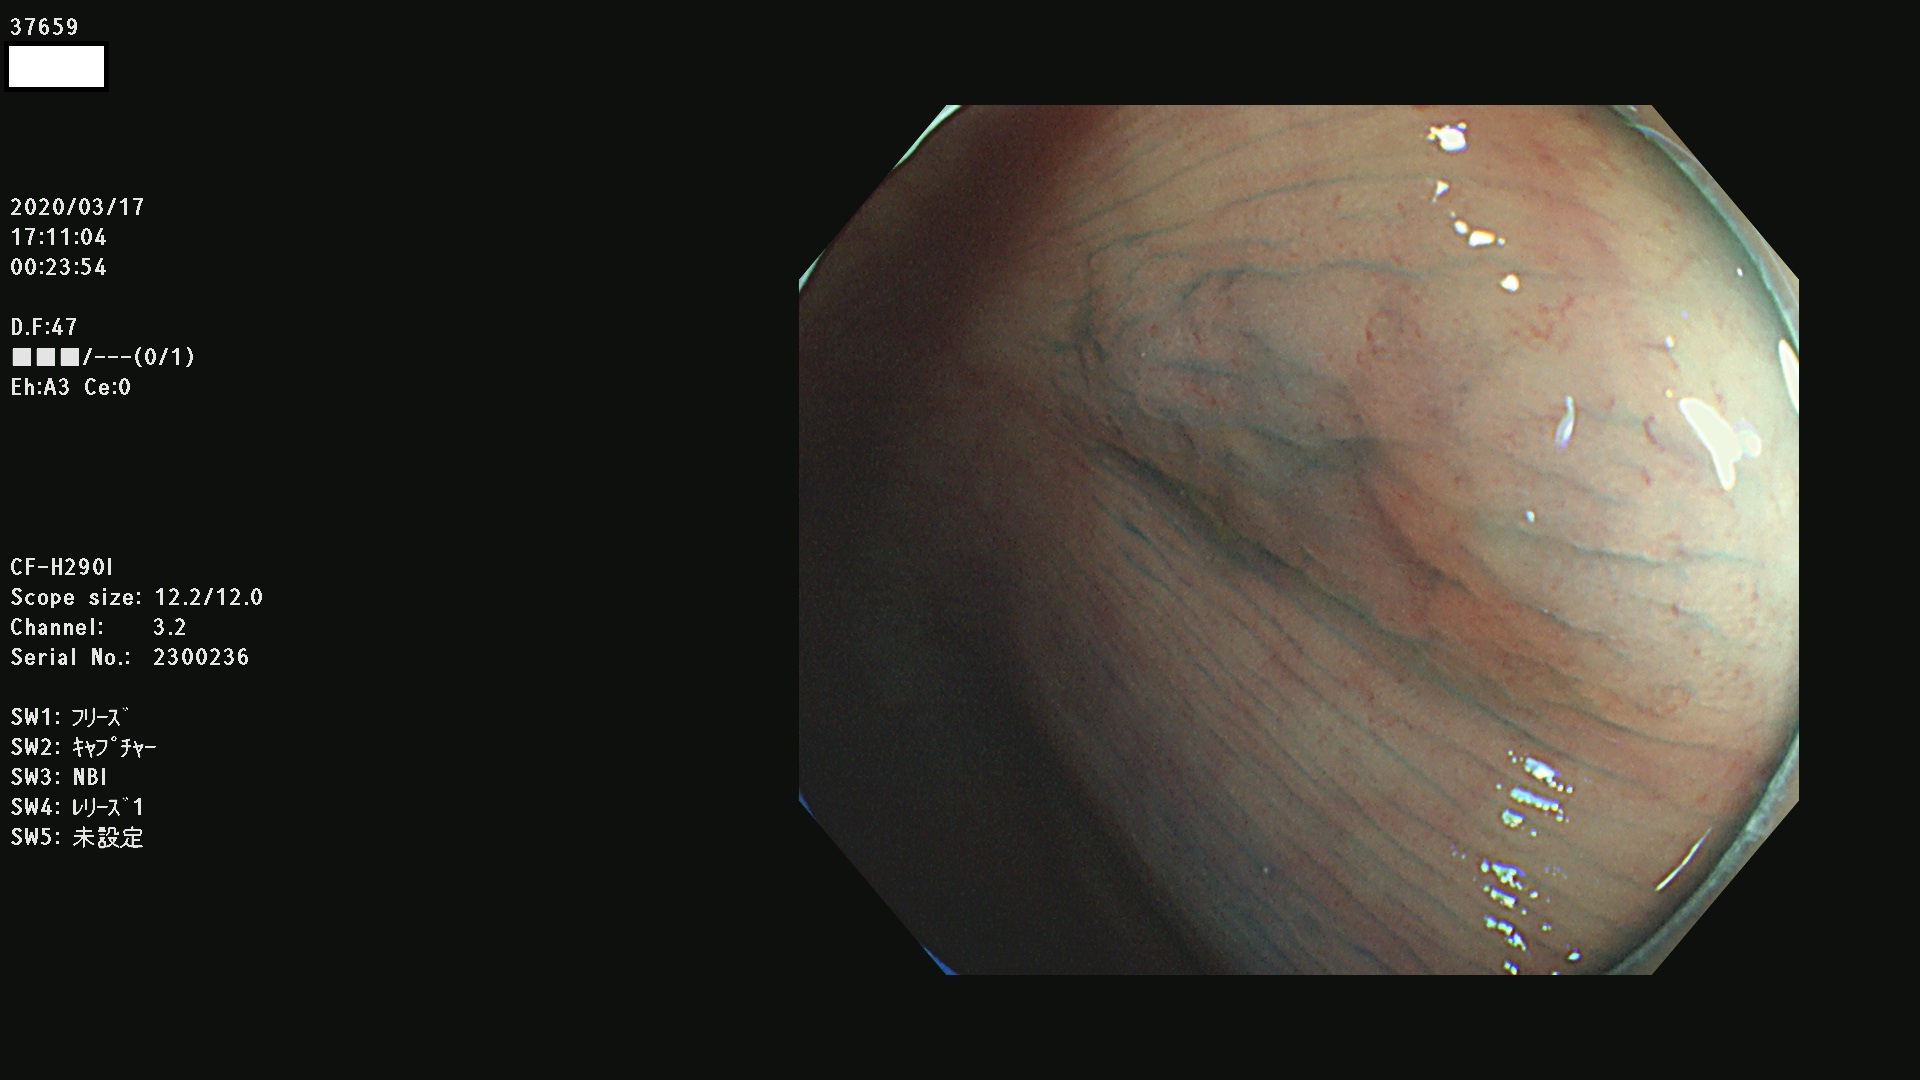

37600 37601 37602 37603 37604 37605 37606 37607 37608 37612 37614 37616 37618 37619 37620 37621 37622(SSAPのみ) 37623(SSAPのみ) 37624 37626 37627 37628 37629 37632 37633 37635 37636(SSAPのみ) 37639 37640 37641 37642 37643 37644 37647(SSAPのみ) 37648 37649 37650 37652 37653 37655 37657 37659 37660 37662 37664 37666 37668(SSAPのみ) 37670 37671 37672 37676 37677 37678 37679 37680 37682 37684 37685(SSAPのみ) 37686 37687 37688 37689 37690 37691 37692(SSAPのみ) 37693 37694 37695 37696 37697 37699

発見困難で危険性の高い平坦型病変(上記100名より抽出)